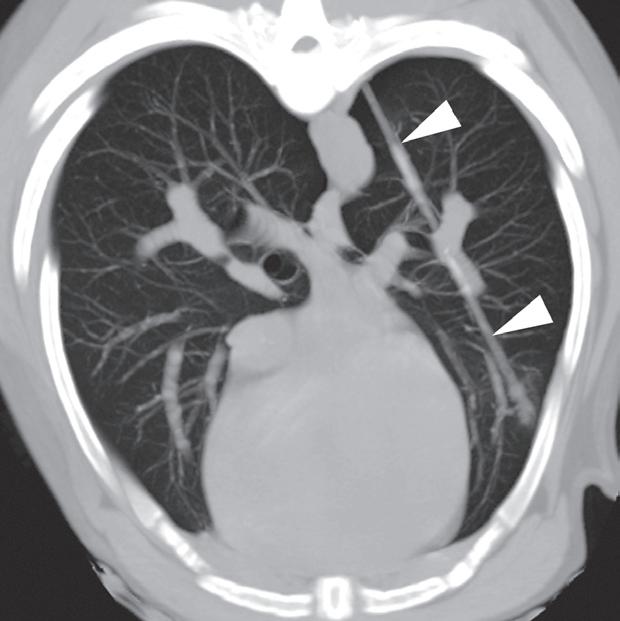

Badanie wykonano u dorosłego, kastrowanego kota domowego krótkowłosego z występującym od kilku miesięcy kaszlem i utratą masy ciała. W ostatnim czasie u pacjenta obserwowano postępujący wysiłek oddechowy. Poprzeczne obrazy TK skupione na dwóch kolejnych żebrach, widoczne od doczaszkowego do doogonowego, ukazują w części bliższej przemieszczone lewostronne złamania (a, b – duże groty strzałek). Oba złamania są minimalnie przemieszczone i mają widoczne proliferacyjne zmiany, niełączące jeszcze odłamów kostnych. Złamania dotyczą sześciu kolejnych żeber po lewej stronie (c). Zmiany w płucach obejmowały znacznego stopnia, uogólniony odczyn okołooskrzelowy (a, b), niedodmę i konsolidację płata dodatkowego płuc (b – strzałka) oraz rozstrzeń oskrzeli (a, b – małe groty strzałek). Popłuczyny oskrzelowo-pęcherzykowe (BAL) wykazały ropne zapalenie, wyhodowano szczep Mycoplasma. Założono, że złamania były wynikiem cyklicznych urazów przeciążeniowych, spowodowanych przedłużonym zwiększonym wysiłkiem oddechowym